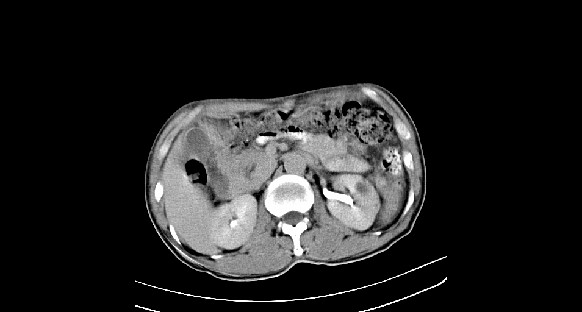

男性,70岁,体检b超发现左肾占位,请各位战友发表一下观点

左肾有两个病灶,且较大的病灶内可见点状钙化灶,增强扫描边缘也是呈渐进性强化,中央部分未见明显强化